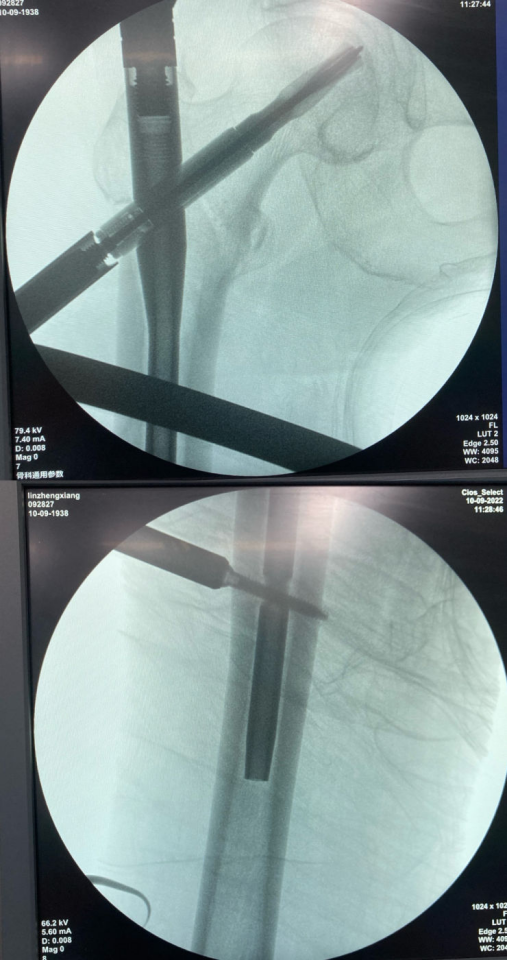

术中,麻醉科医生严格控制麻醉药品的剂量和浓度,密切观察病情,监测各项生理指标,确保老人的生命体征平稳。副院长张有文为百岁老人实施了右股骨粗隆间骨折闭合复位髓内钉内固定术,历时40分钟,手术圆满完成。